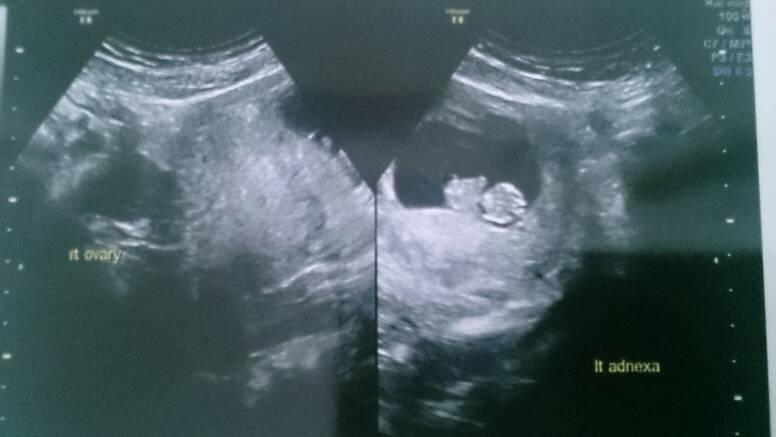

Sorki bo zdjęcie se zdjęcia..

Przez brzuch wszystkie, pierwsze 8t3 drugie dwa 8t6d.

Lilith o kurcze super widac dzidzie! Dzieki za zdjecia, to moze ja teraz tez bede sie upierac przy usg brzusznym? Sama nie wiem....W sumie to mam troche metlik w glowie, czesc osob mowi ze usg zadne nie ma wplywu na malucha, czesc mowi ze kazde usg ma wplyw a to dowcipne to juz w ogole inwazyjne grzebanie i lepiej tego nie robic.... Wkurza mnie to,mze kazdy mowi co innego, a ze jestem po stracie to jestem podatna na te wszystkie dobre rady:/:(

Lilith A zdjęcia bomba! Pierwszy raz takie widzę i nie mogę się napatrzec :D